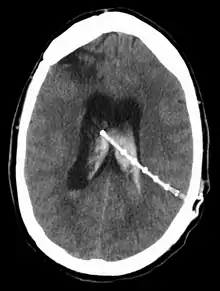

![]() A diagram of a typical brain shunt | |